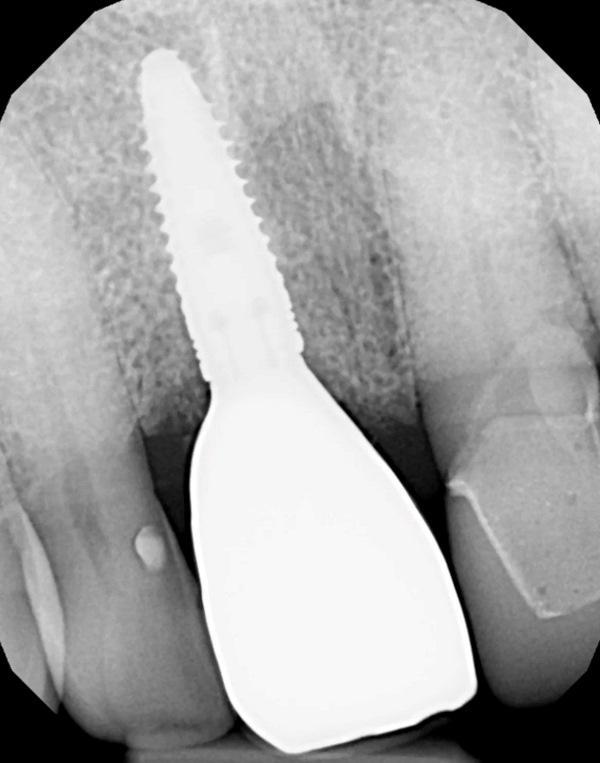

Коронка снята, канал доступа к винту в абатменте закрыт тефлоновой лентой. Коронка зафиксирована на абатменте стеклоиономерным цементом (GC FujiCEM 2, GC America). После отверждения цемента излишки по краю удалены зондом. Окклюзия проверена и при необходимости откорректирована (Фото 13). Выполнена прицельная рентгенограмма для документирования окончательной реставрации (Фото 14) и получен интраоральный скан (Primescan) для изготовления ночной каппы.

Фото 14. Прицельная рентгенограмма коронки на имплантате, зафиксированной на индивидуальном абатменте, демонстрирует уровень кости на гребне относительно уровня имплантата.

На годовом профилактическом осмотре мягкие ткани вокруг реставрации с опорой на имплантат без признаков воспаления и выглядят здоровыми (Фото 17). Выполнена прицельная рентгенограмма для контроля уровня кости на гребне (Фото 18). Гребневая кость, подсаженная при установке имплантата, сохранялась на необходимом уровне, что указывает на поддержание здоровой кости на уровне гребневой части имплантата.

Фото 18. Прицельная рентгенограмма через 1 год после фиксации реставрации демонстрирует сохранность уровня кости на гребне.